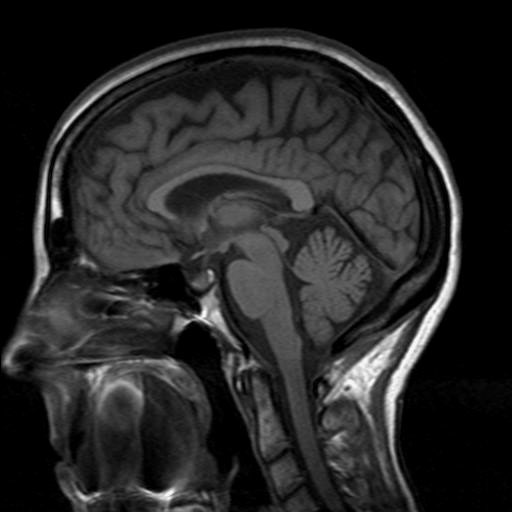

This image shows a slice in which plane of section?

Sagittal